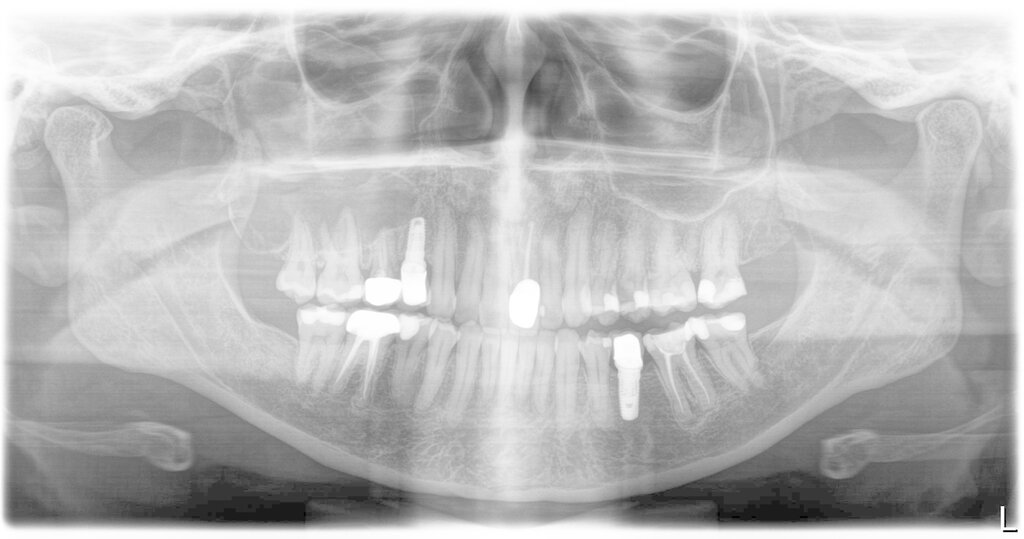

Neben der Frage nach der Chance des Zahnerhalts stellen Patienten häufig die Frage, ob sie durch die WSR Nachteile zu erwarten hätten, wenn sie sich später, bei Fehlschlag der WSR für ein Implantat entscheiden würden (Abbildung 6).

Tatsächlich ist die Datenlage zu dieser Fragestellung sehr dünn. Die Schwierigkeit der wissenschaftlichen Aufarbeitung und damit auch das Fehlen von Publikationen liegt in der Notwendigkeit einer sehr hohen Fallzahl sowohl bei der WSR und als auch bei der Implantattherapie, um Fälle zu finden, wo nach zunächst durchgeführter und später gescheiterter WSR der Patient dann an dieser Stelle tatsächlich ein Implantat bekommen hat und anschließend noch eine akzeptable Zeit in der Nachbeobachtung war. So war bei einer Studie von Saleh et al. [2021] das Screening von 1.241 Wurzelspitzenresektionen und über 9.000 Implantaten in einem 15-Jahres-Zeitraum notwendig, um am Ende 25 Studienteilnehmer für eine retrospektive Untersuchung einschließen zu können.

Hierzu wurde ein Datensatz mit 816 Implantaten bei 598 Patienten mit verfügbaren Röntgenbildern der extrahierten und ersetzten Zähne ausgewertet. Die Behandlungsfälle wurden in eine Gruppe mit (Gruppe A) und eine Kontrollgruppe ohne vorangegangene Wurzelspitzenresektion (Gruppe B) eingeteilt. Ein möglicher Zusammenhang zwischen der vorangegangenen Wurzelspitzenresektion und der Notwendigkeit einer späteren hartgeweblichen Augmentation mittels Schalentechnik beziehungsweise der klassischen Blockaugmentation wurde statistisch untersucht.

Insgesamt 437 Implantate (Gruppe A: 42, Gruppe B: 395) bei 309 Patienten, die am Nachsorgeprogramm teilnahmen, wurden darüber hinaus im Hinblick auf das Implantatüberleben und den periimplantären Knochenverlust ausgewertet. Die Fünf-Jahres-Implantatüberlebensrate wurde mit dem Kaplan-Meier-Schätzer berechnet. Der periimplantäre Knochenverlust wurde auf Röntgenbildern bis zu fünf Jahre nach Implantatinsertion vermessen.

Bei 11,5 Prozent des Gesamtkollektivs (94 Fälle) war eine Wurzelspitzenresektion durchgeführt worden. In 19,1 Prozent der Fälle der Gruppe A (mit vorangegangener WSR) und 26,6 Prozent der Fälle der Gruppe B (ohne WSR) wurde im Rahmen der anschließenden Implantattherapie eine hartgewebliche Augmentation durchgeführt: Der Unterschied war nicht signifikant (p = 0,12). Auch bei der der Fünf-Jahres-Implantatüberlebensrate (Gruppe A: 96,6 Prozent; Gruppe B: 98,0 Prozent) und dem marginalen periimplantären Knochenverlust wurden während des Fünf-Jahres-Follow-ups zu keinem Zeitpunkt signifikante Unterschiede zwischen beiden Gruppen berechnet [Kreisler et al., 2022].

Abgeschlossene apikale Defekte heilen nach Extraktion in der Regel problemlos aus und spielen daher für die spätere Implantattherapie keine Rolle. Problematisch sind Defekte, die bedingt durch eine ausgedehnte apikale Osteolyse keine oder fast keine vestibuläre Lamelle aufweisen (Abbildung 7), wobei dieses Problem bei einer Extraktion als Differenzialtherapie unverändert bleibt. Darüber hinaus können Fälle mit einer sekundär (nach der WSR) aufgetretenen Längsfraktur bekanntermaßen zu ungünstigen Knochendefekten führen.

Die Daten zeigen, dass eine vorangehende WSR die mögliche spätere Implantattherapie nicht negativ beeinflusst. Dies trifft sowohl für den Behandlungsaufwand als auch für die Implantatprognose zu. Es ist aus unserer Sicht wichtig, dies in jedem Aufklärungsgespräch auch so zu kommunizieren.